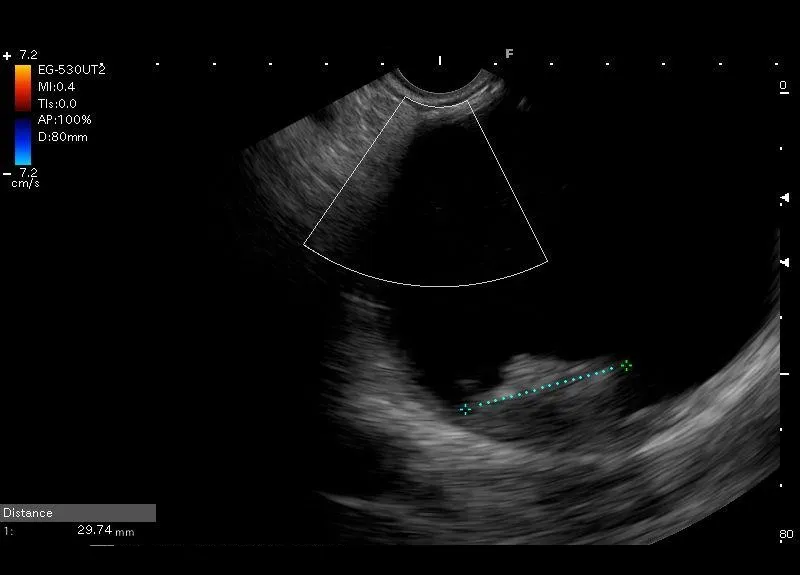

Zmiana torbielowata z hiperechogenicznym obszarem przyściennym